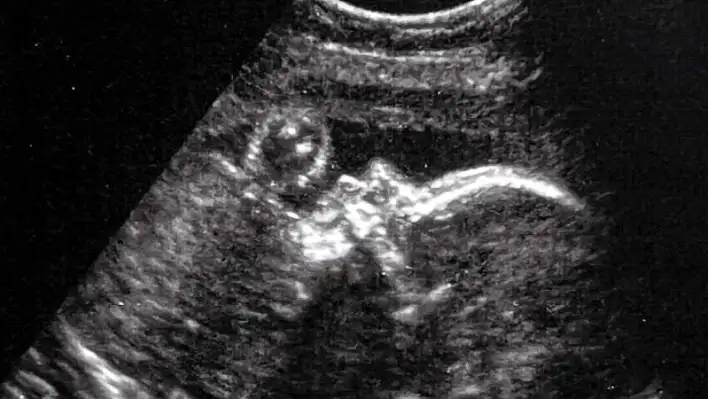

Doğmamış bebeğe anne karnında beyin ameliyatı

CNN televizyonunun haberine göre, doktorlar, bebekte tespit ettikleri nadir görülen “Galen ven malformasyonu” hastalığının doğum sonrasında ciddi beyin hasarları ve kalp yetmezliği gibi sorunlara yol açabileceğini söyledi.

Ultrason kullanarak atardamarın tespiti yöntemiyle gerçekleştirilen ameliyat, bebeğin henüz anne karnındayken gerçekleştirildi. Doktorlar, annenin karnından uzun bir iğneyi bebeğin beyninin etkilendiği kısma yönlendirdi ve daha sonra damarlara geri akışı engellemek amacıyla bir madde enjekte etti.

Ameliyat başarıyla gerçekleştirildi ve henüz doğmamış bebeğin doğumundan sonra ölümcül kalp yetmezliği ve nörolojik rahatsızlıklar gibi ciddi hastalıkların ortaya çıkmasını engellendi. Hastalığa sahip tüm bebeklerin yüzde 50 ila 60’ında doğumdan hemen sonra ciddi rahatsızlıkların ortaya çıktığı belirtilirken, yaklaşık yüzde 40’lık bir ölüm oranı da bulunuyor.

Ameliyatı gerçekleştiren doktorlar, Denver adlı bebeğin ameliyattan sonra sağlıklı bir şekilde dünyaya geldiğini ve yaklaşık iki ay sonra hala sağlıklı olduğunu belirtti. Kalp yetmezliği için herhangi bir ilaç kullanmayan ve ek müdahaleye ihtiyaç duymayan bebeğin durumunun iyi olduğu açıklandı.